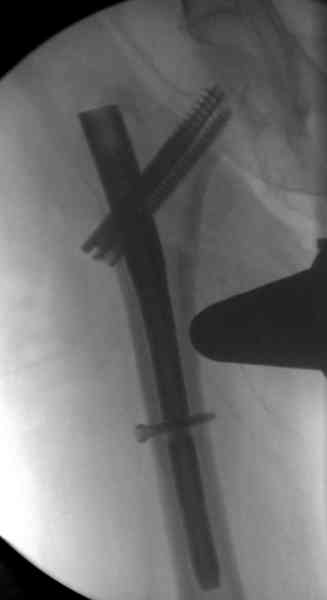

Здесь сканнированные снимки импланта и операционные снимки больной.